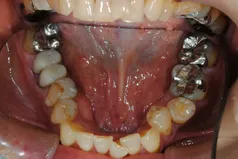

[症例2]

治療前は臼歯部は保険の冠のため金属色が目立ちます。上顎の前歯はセラミックですが、古いタイプの治療法ため裏側に金属が露出しています。

矯正治療後に部分被せも含めて全てセラミックで治療しました。

右下6番は歯を真ん中で分割して2本の冠が入っていましたが、抜歯してインプラントが入っています。

上下顎とも金属色の見えない美しい歯並びになりました。

- 治療期間:約1年

- 治療費:240万円

- 治療回数:26回